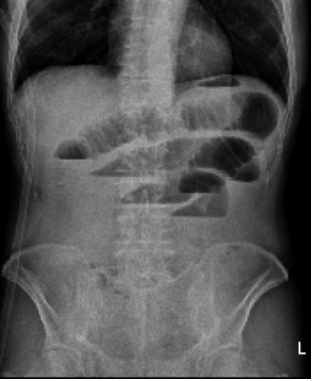

36 一位 80 歲男性,因昨日開始有腹脹及嘔吐的症狀來急診就診,病人表示之前也有過幾次類似的症狀, 身體診查顯示體溫為 36℃,呼吸每分鐘 16 下,心跳每分鐘 80 下,腹部檢查顯示下腹有一開刀的疤 痕、腹部脹大(distended)、無壓痛(tenderness)的症狀,放置鼻胃管後,病人自覺症狀改善,追 蹤的影像學檢查如下圖,下列敘述何者錯誤?

(A)病人可能有缺水(dehydration)狀況,需給予輸液補充(fluid resuscitation)及監測尿量 (B)病人需要大量給予水分時,可以考慮放置中央靜脈導管(central venous catheter)以監測水分給予 的狀況 (C)若出現腹部疼痛或 peritoneal sign,則表示有腸壞死的可能性 (D)支持性療法(supportive care)不適用於這位病人